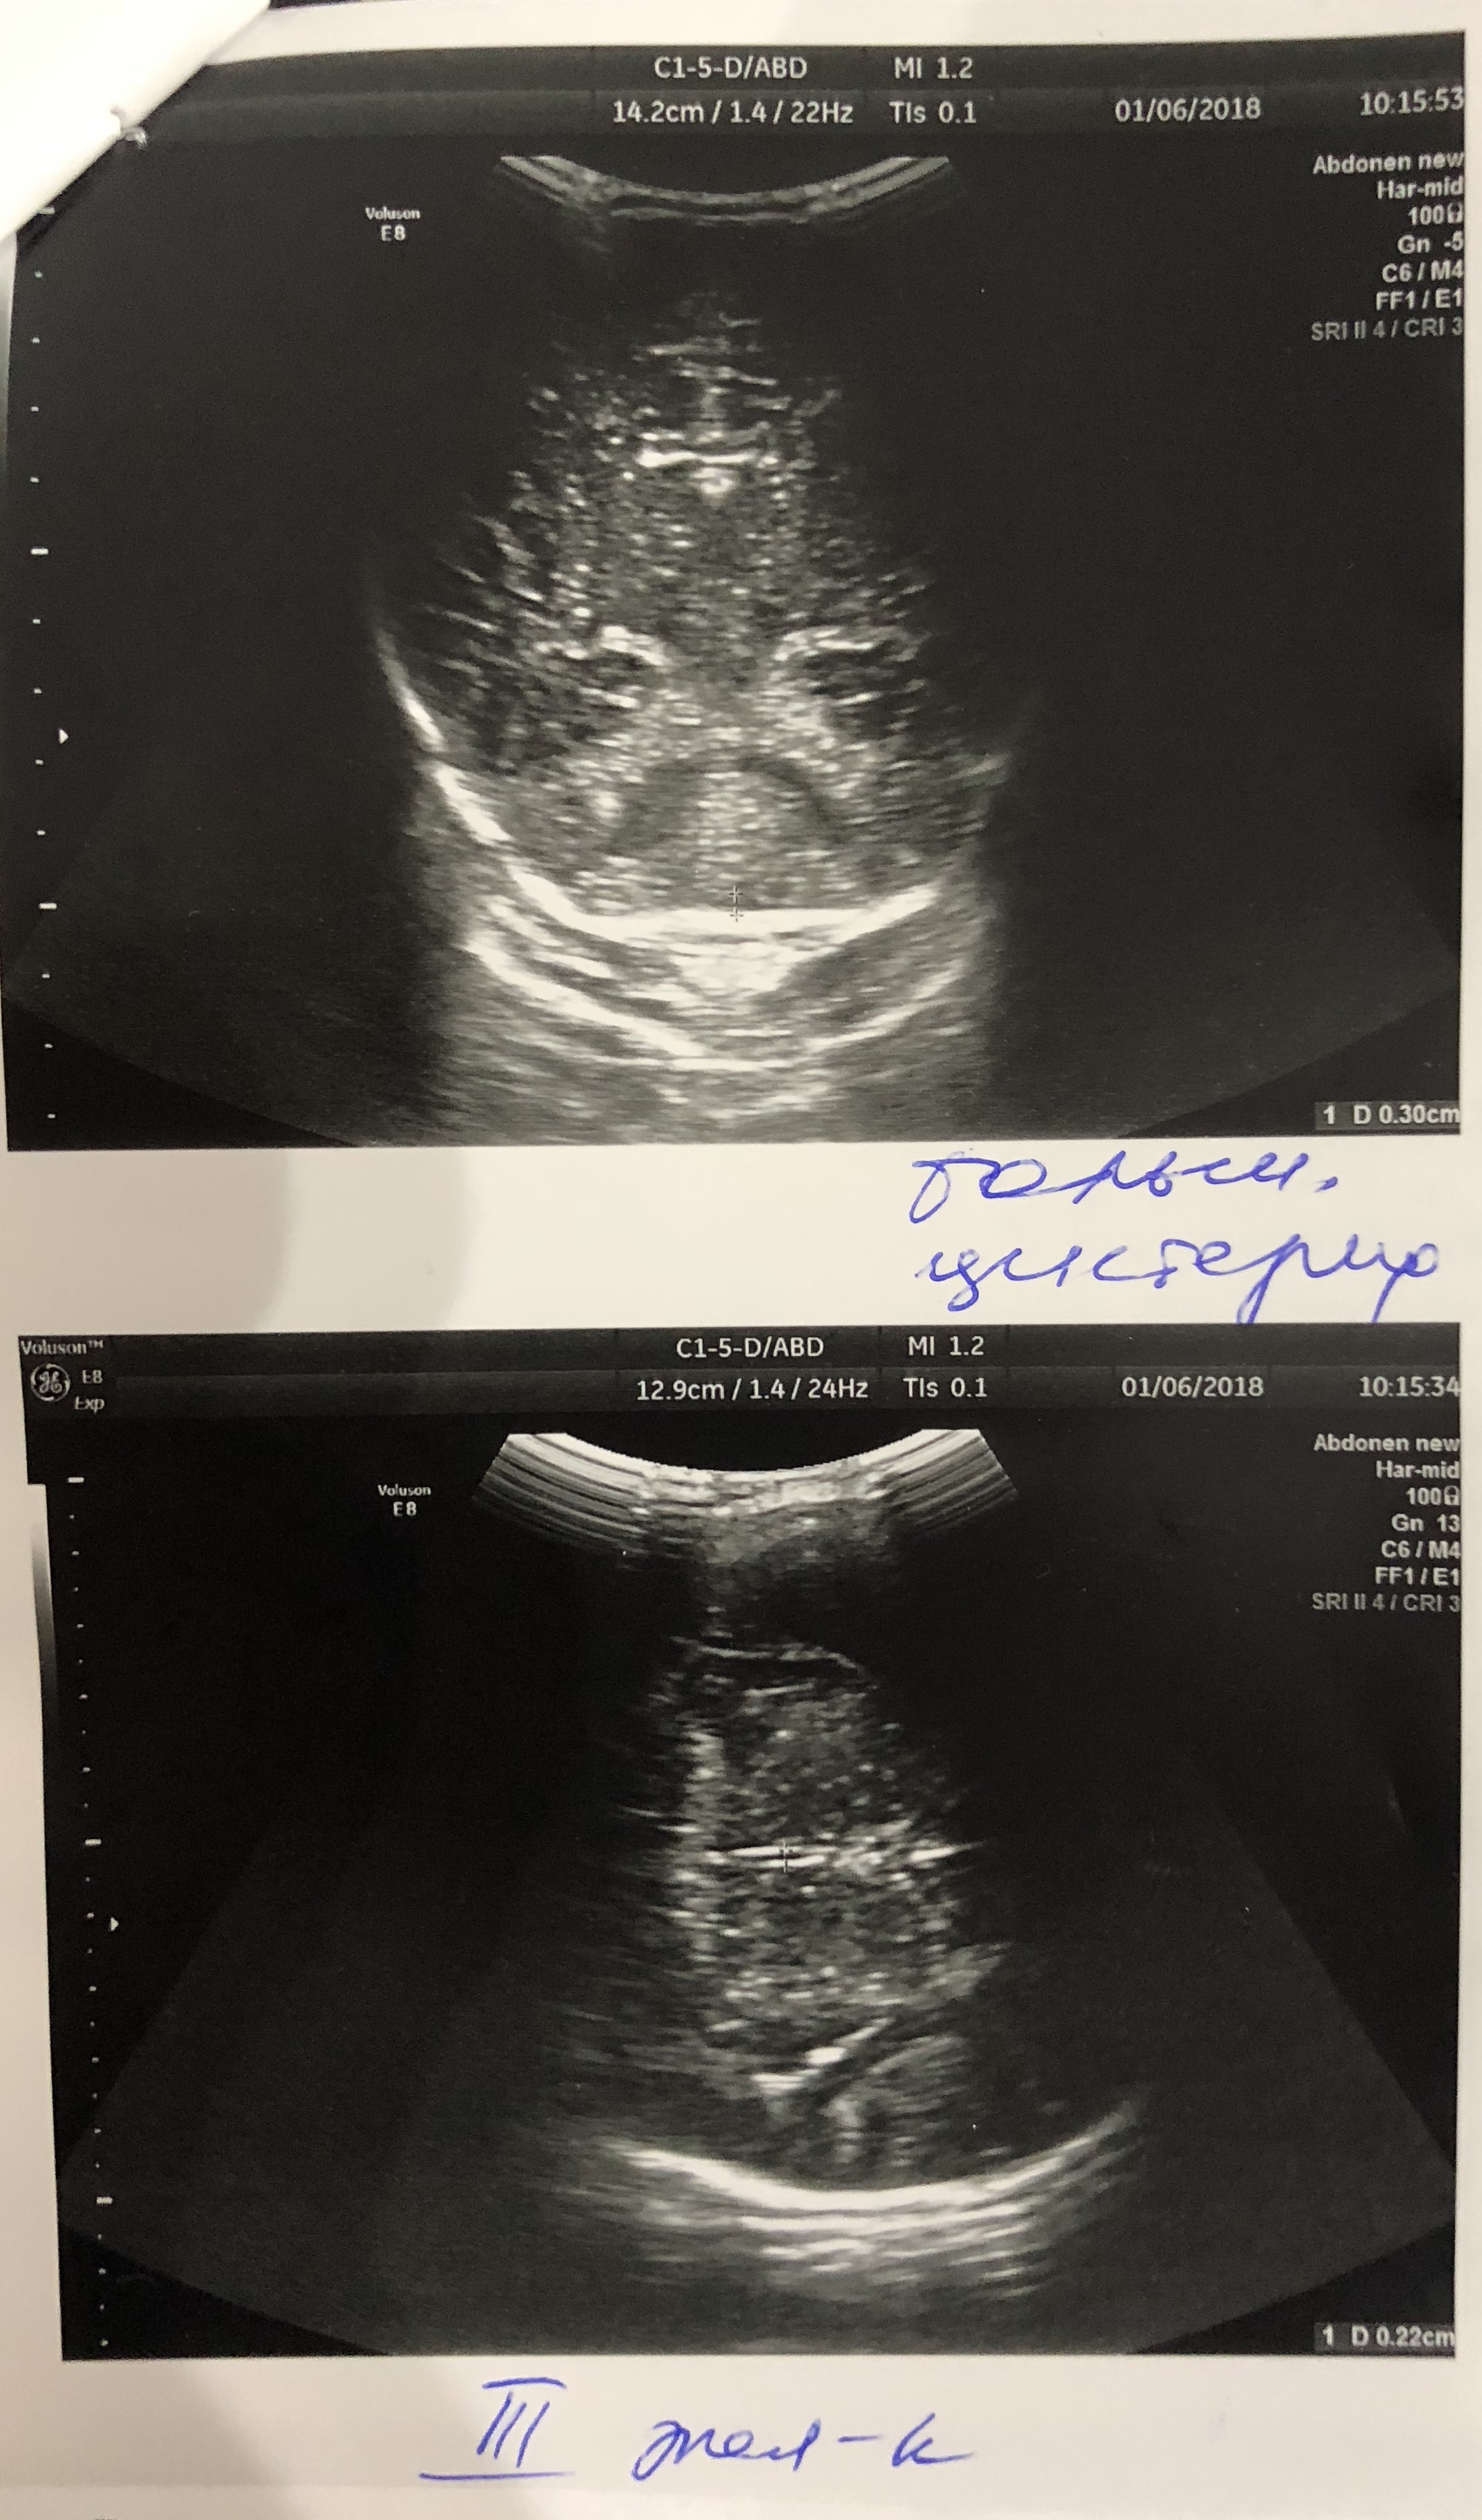

Ходили на НСГ, показало увеличение ЛСК по Вене Галена 20 см/с . Так же обнаружили эхопризнаки сочетанного расширения наружного и внутреннего ликворных пространств (БЖ и САП) . Значения: САП - 7,5 мм БЖ - Левый (передний рог - 5,6 мм, тело - 6 мм) - Правый (передний рог - 5,8 мм, тело - 6,3 мм) Были у офтальмолога, проверяли глазное дно . Все в норме .

Венозный компонент: кровоток в вене Галена не изменен ЛСК =16,8 см/сек (выше возрастной нормы, угрожаем по развитию гипертензионно-гидроцефальному синдрому)